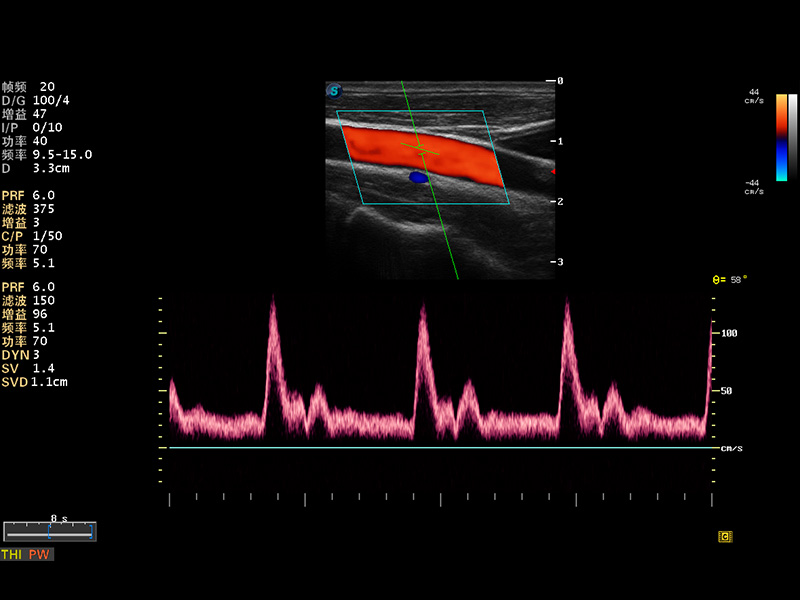

S8 EXP便携式彩色多普勒超声诊断仪是亚星官网研发的高端全身应用型便携彩超。高通道的VIS平台融合可视化(Visual)、智能化(Intelligent)和人性化(Smart)的特点,配以亚星官网自主研发生产的探头大家族,使您能够快速、准确的获得病人信息,提高工作效率的同时减轻疲劳。

成像技术

多波束形成器